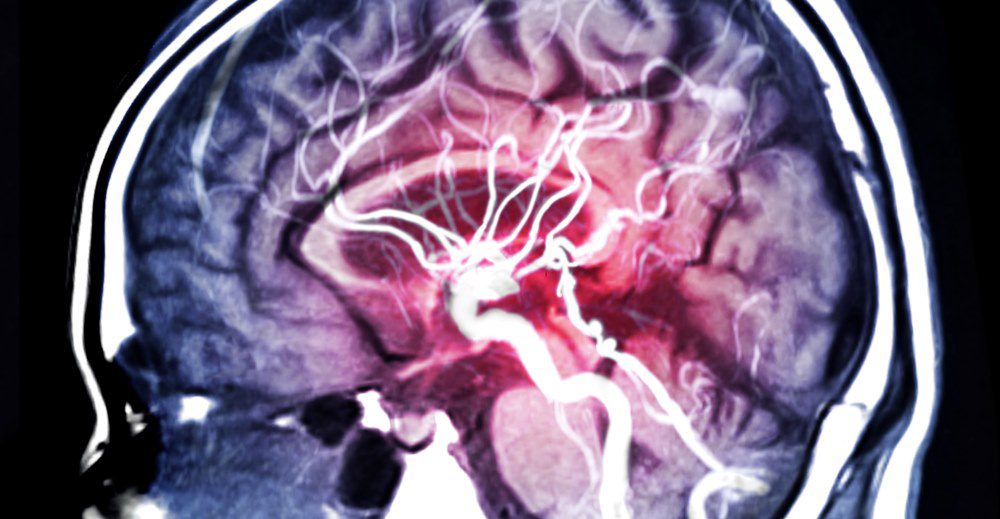

“Do not ignore this… read it in full!” This isn’t just a catchy phrase to grab your attention; it is a genuine call for awareness about a condition often known as the “silent killer.” An aneurysm is a bulge or ballooning in the wall of an artery. If left undiagnosed, it can rupture, causing life-threatening internal bleeding in a matter of moments.

1. Ruptured Brain Aneurysm

- The worst headache of your life: Medically described as a “thunderclap” headache, this is a sudden, severely intense pain that feels completely different from any headache you have ever experienced.

- Nausea and vomiting: Often accompany the intense, blinding headache.

- Stiff neck: Noticeable pain or stiffness that makes it difficult to move your neck freely.

- Vision problems: This can include blurred or double vision, extreme sensitivity to light, or a drooping eyelid.

- Severe neurological changes: Such as sudden confusion, loss of consciousness, weakness or numbness on one side of the face, or even a seizure.

- Dilated pupils: One or both pupils may become abnormally enlarged.